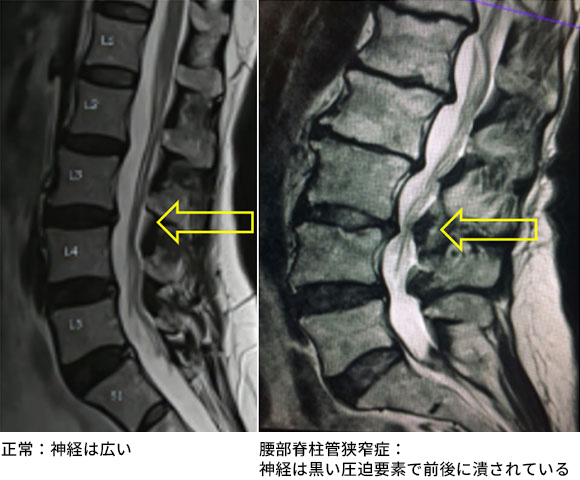

←は圧迫されている神経。画面左が臍側、S1より下は尾底骨になります。神経は画面を緩やかに縦に流れている白い領域の中の、グレーの線維状のものです。

腰部脊柱管狭窄症は、脊柱管(神経の通り道)が狭くなる良性の病気です。加齢による骨や靭帯の肥厚が原因となり、立位や後屈で神経が圧迫され、前屈で症状が緩和します。